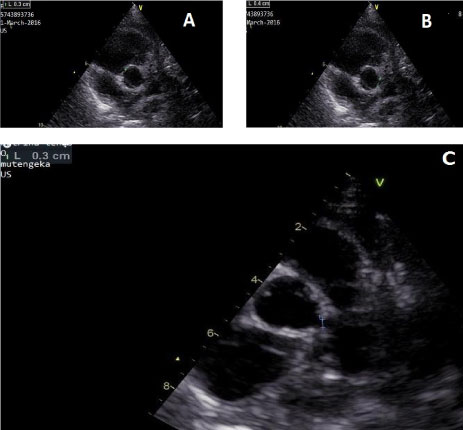

Treatment was started on day 22 with high dose infusion IVIG at 2 g/kg (single dose) and high dose aspirin at 100 mg/kg in four divided doses for 4 days and was stepped down to 3 mg/kg for 6 weeks. The infant markedly improved with fever subsiding within 24 hours of commencing treatment. Serial follow up echocardiograms showed resolution of the dilated coronary arteries over time until child was 3-years old when the coronary arteries were of normal diameter for her body surface area (see Table 3 and Figure).

Figure 1: Figure showing echocardiography pictures of the dilated coronary arteries at 6 month after initiation of treatment and at 3 years of age. A) Shows dilated right coronary artery 3 mm in diameter; B) shows dilated left main coronary artery 4 mm in diameter; C) shows the left main coronary artery measuring 3 mm in diameter at 3 years of age, right coronary artery also measured 3 mm in diameter (not shown in this picture). View Figure 1